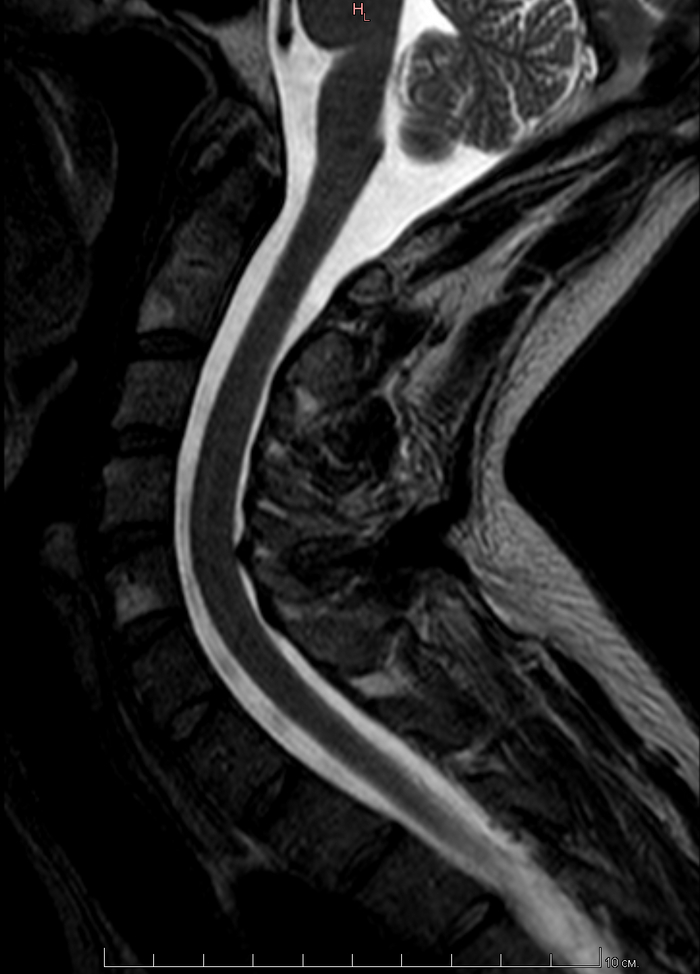

МРТ всех отделов позвонка

К этому посту Мое первое МРТ в 32 годика и этому Пикабу, нужна помощь по здоровью(Невролога(Но это не точно))

Пришло заключение от МРТ центра, я понимаю что надо идти еще на консультацию невролога и т.д. Но может кто из пикабушников сможет расшифровать по нашему, что и как.

Ну и что мне дальше делать.

Делал я МРТ всех отделов позвоночника. Лежал в аппарате полтора часа.

По самому МРТ, может кто тут разбирается, я приложу пару снимков, так как заключение будет только в понедельник. Может кто и поможет. Но, как сказала врач в центре МРТ, с моей симптоматикой, надо делать МРТ головного мозга =(